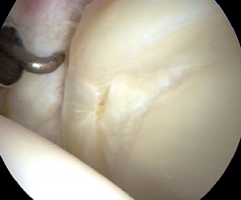

髋臼盂唇损伤因素包括创伤、退变、发育不良和髋关节撞击综合征(Femoroacetabular impingement syndrome ,FAI)。髋臼盂唇损伤后将改变髋关节的生物力学机制,引起髋部或腹股沟区疼痛,造成关节不稳,增加关节应力,最终导致骨性关节炎的发生。(左图:正常的盂唇;右图:盂唇撕裂)